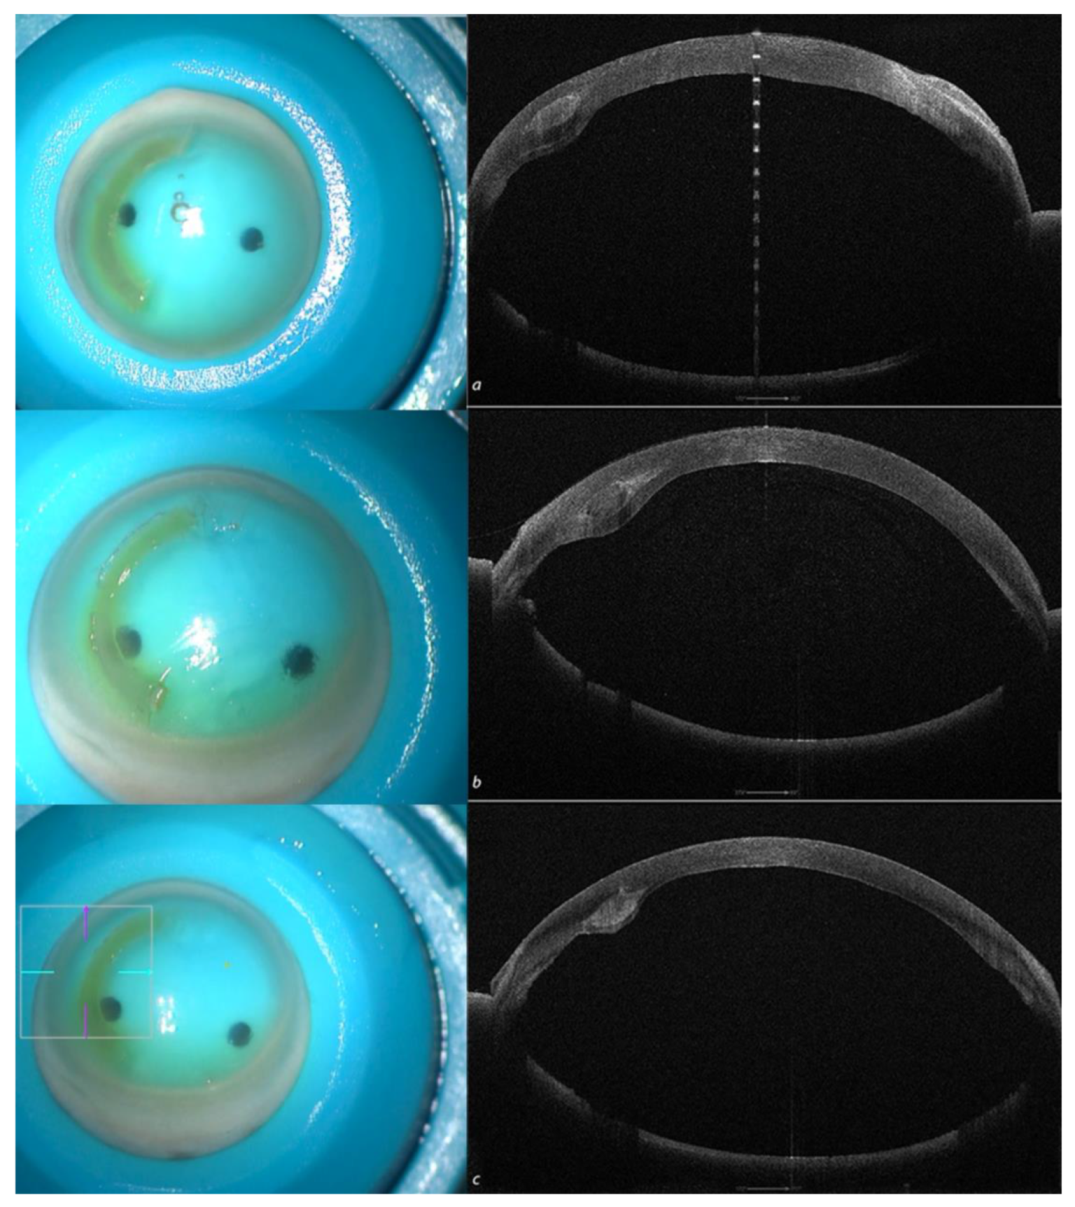

The test was successful, independent of the implant depth (50, 60 and 70%), as shown in Figure 4.

Figure 4. Recipient corneas with Crosslinked All femtosecond laser-cut CAIRS (AFXL CAIRS) implants at different depths, well-visualized by high-resolution (HR) Anterior Segment OCT Tomography performed with the MS 39 (CSO, Florence, Italy) at 50% (a), 60 % (b) and 70% (c).